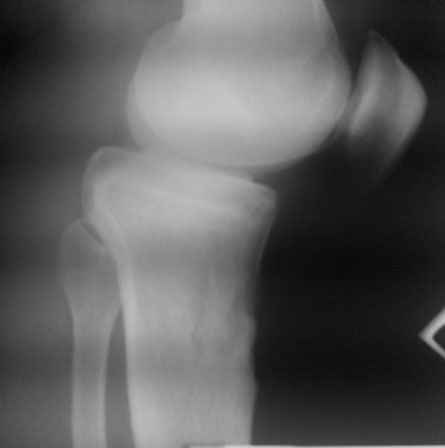

По видимому, тогда было повреждение задней крестообразной связки,

рекурвация голени стала устойчивой, плато имеет неправильный угол

наклона, а в верхней трети большеберцовой кости формируется маршевый

перелом.

Объективно. Боли при пальпации нет, движения практически в полном

объеме. Рекурвация внешне совершенно очевидная. Положение голени

устойчивое.

Растущая киста Бейкера говорит о начале декомпенсации со стороны

сустава, как я понимаю.

Что мы можем предложить пациенту. Ваши прогнозы по развитию маршевого

перелома. Стоит ли сейчас предлагать коррекцию рекурвации. Что делать

с «задним выдвижным положением», ибо это уже не

«ящик». Нет даже колебания вперед-назад.